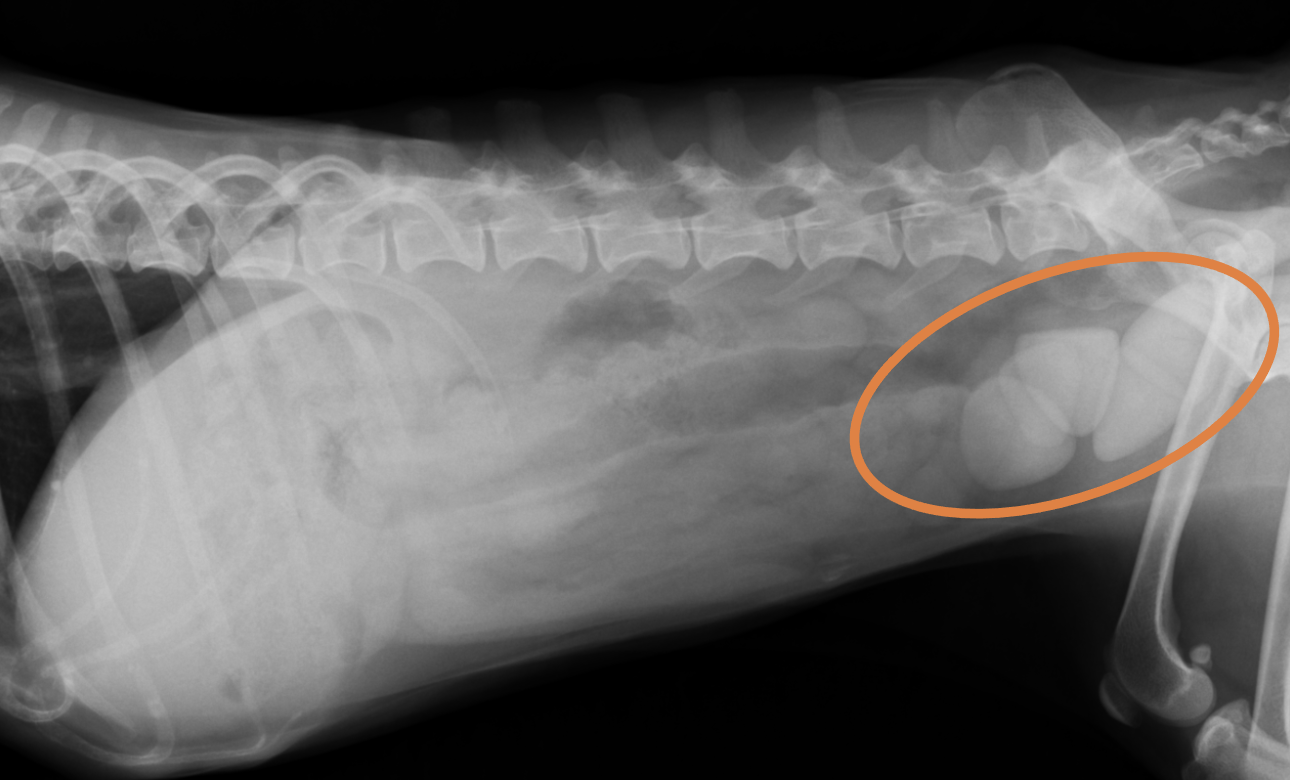

整形外科の雑誌であるVeterinary and Comparative Orthopaedics and Traumatologyに磯野の論文である「Tibial Torsion Malalignment in Small Dogs with Medial Patellar Luxation」が掲載されました。パテラ内方脱臼に対し、脛骨粗面と足根骨の捩れが関与しているをことを示し、その指標の一つを提言した内容になります。ご興味ある方はご覧ください。